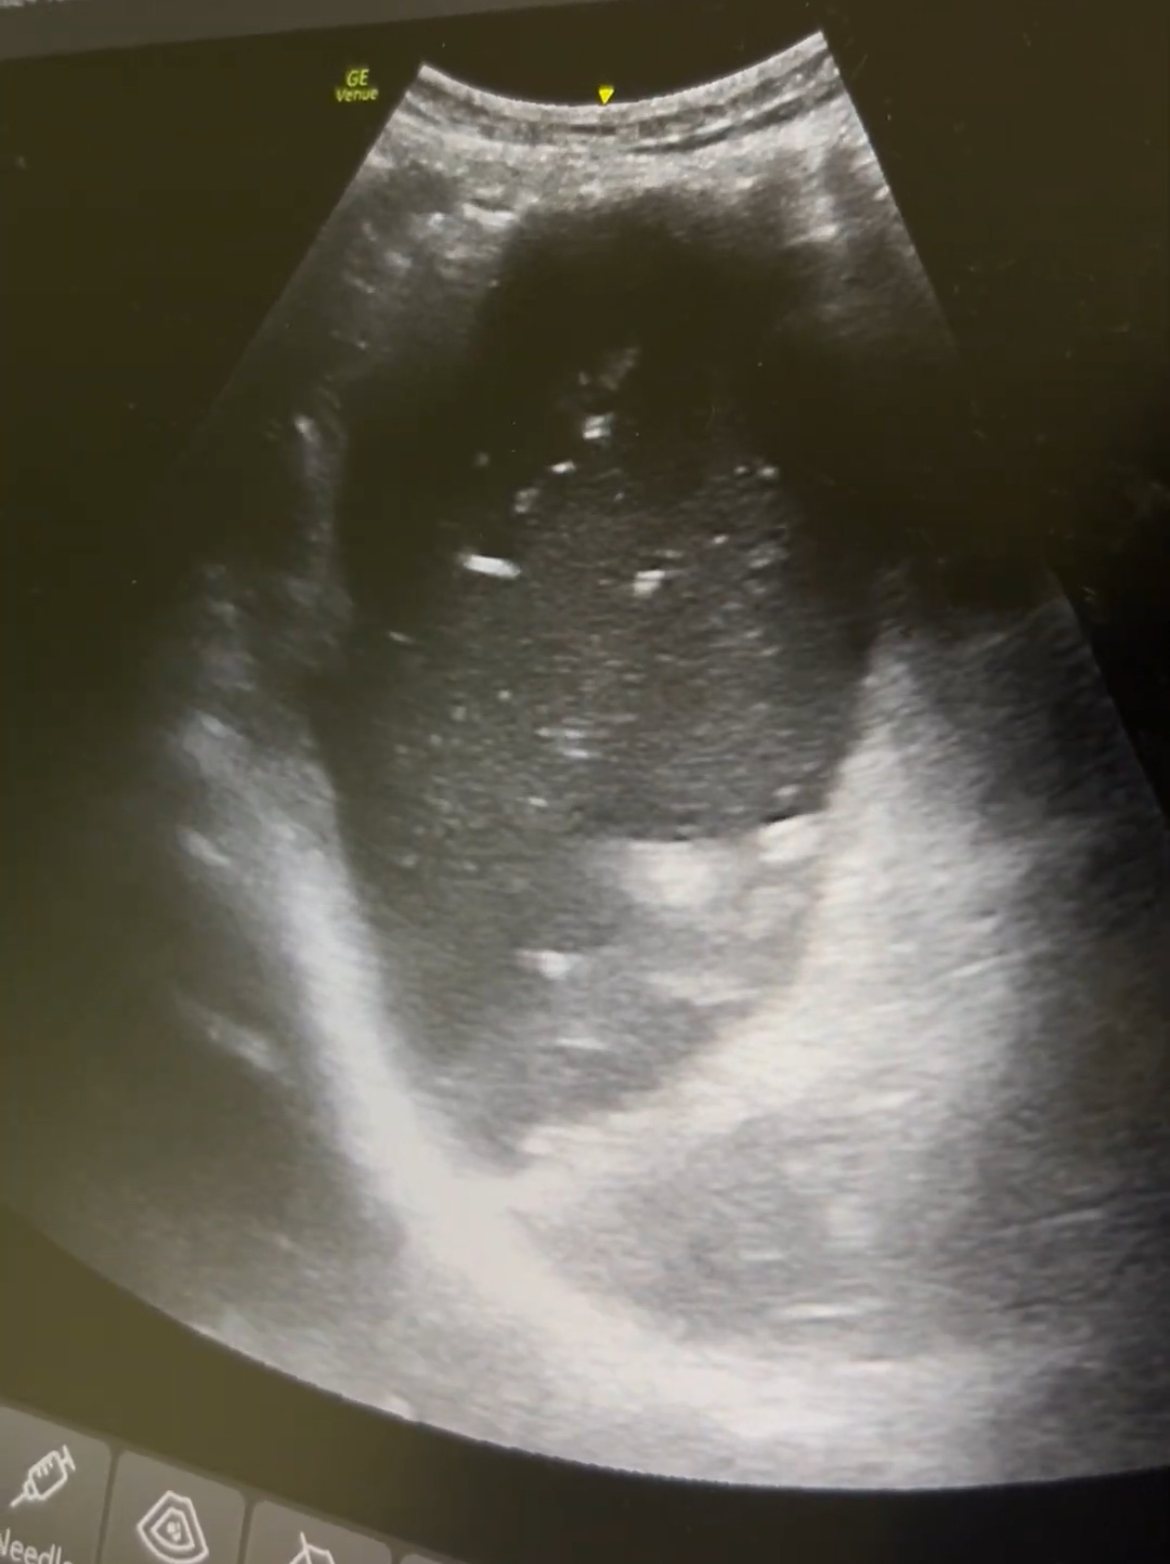

Ante AP de cirugía, dolor abdominal y vómitos, se realiza rx abdominal que resulta normal. Dada la alta sospecha, se realiza ecografía: gran cámara gástrica con contenido en su interior con dinámica «en lámpara de lava». Además, asas de intestino delgado dilatadas (diámetro 2,9 cm) con movimiento de peristalsis y rebote y edema de pared. Compatible con obstrucción intestino delgado.